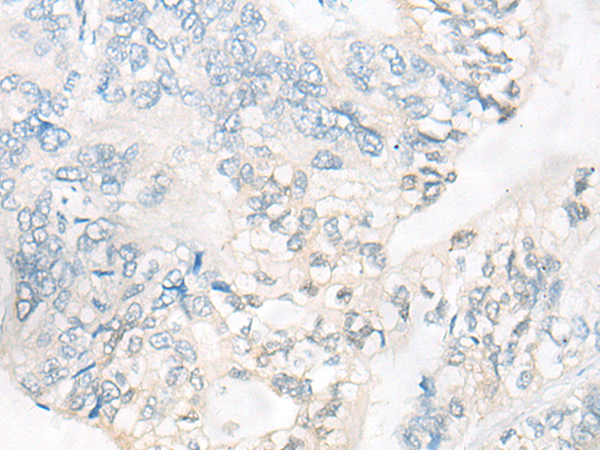

分类: 科研抗体货号: P10761别名: KACL; PILAR; UNQ5792应用: IHC反应种属: Human